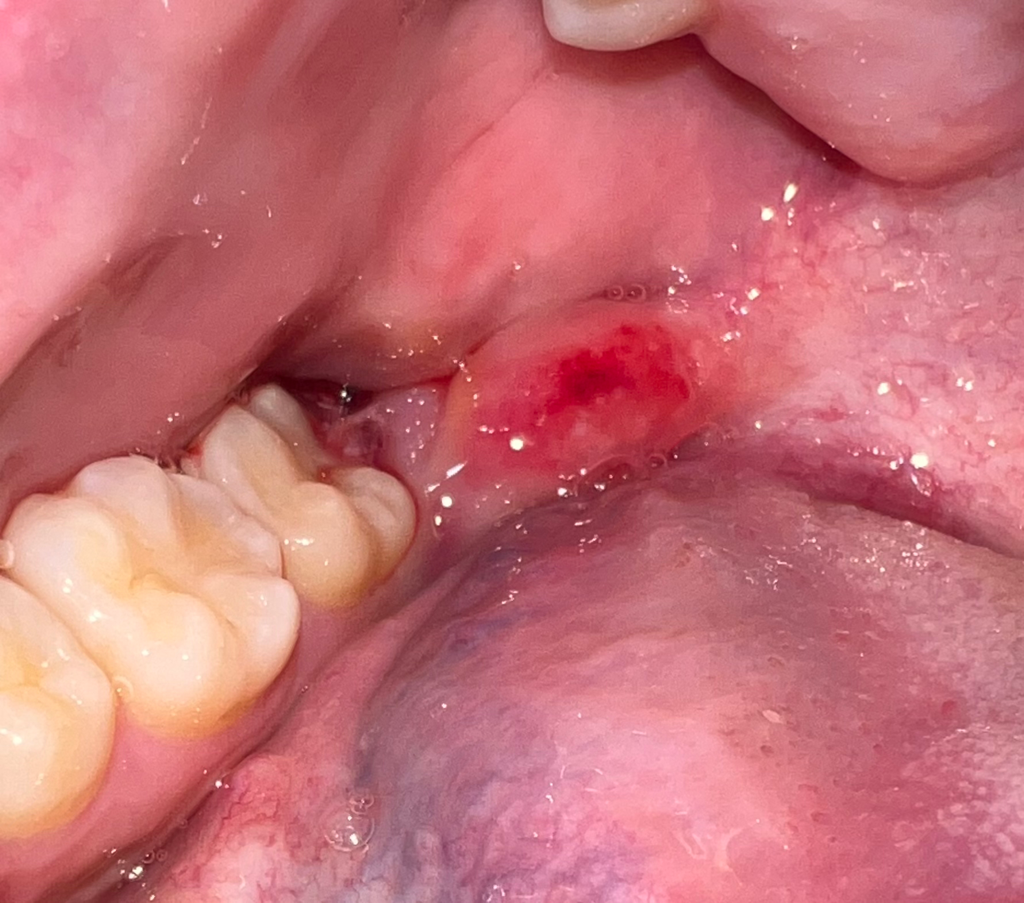

사랑니 발치 후 염증이 난 것인지 궁금합니다

사랑니 발치 후 3일째인데 통증이 안 가라앉아서 보니까

뽑은자리 뒷쪽 잇몸이 빨갛게 부어올랐네요

자연치유과정인지 아니면 문제가 생긴건지 궁금합니다

• 1번 째 사진

• 안녕하세요. 김철진 치과의사입니다.

사랑니 발치로 인한 염증은 아니고 그쪽 살이 씹혀서 그런거 같습니다. 크게 이상이 잇는건 아니니 아프시면 치과에 가셔서 소독한번 받으시면될것같습니다.